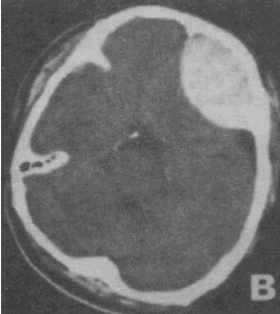

男性,55岁。被汽车撞倒半小时,昏迷状态。急诊平扫CT。检查图像如图所示,诊断最可能是<img border="0" style="width: 264px; he

[单选题]男性,55岁。被汽车撞倒半小时,昏迷状态。急诊平扫CT。检查图像如图所示,诊断最可能是A.脑实质出血B.正常脑CT表现C.硬膜下血肿D.硬膜外血肿E.

[单选题]男性,55岁。被汽车撞倒半小时,昏迷状态。急诊平扫CT。检查图像如图所示,诊断最可能是A.脑实质出血B.正常脑CT表现C.硬膜下血肿D.硬膜外血肿E.

[单选题]男性,55岁。被汽车撞倒半小时,昏迷状态。急诊平扫CT。检查图像如图所示,诊断最可能是A.脑实质出血B.正常脑CT表现C.硬膜下血肿D.硬膜外血肿E.

男性,55岁。被汽车撞倒半小时,昏迷状态。急诊平扫CT。检查图像如图所示,诊断最可能是( )。<br /><img border="0" style="

[单选题]男性,55岁。被汽车撞倒半小时,昏迷状态。急诊平扫CT。检查图像如图所示,诊断最可能是( )。A.脑实质出血B.正常脑CT表现C.硬膜下血肿D.硬膜